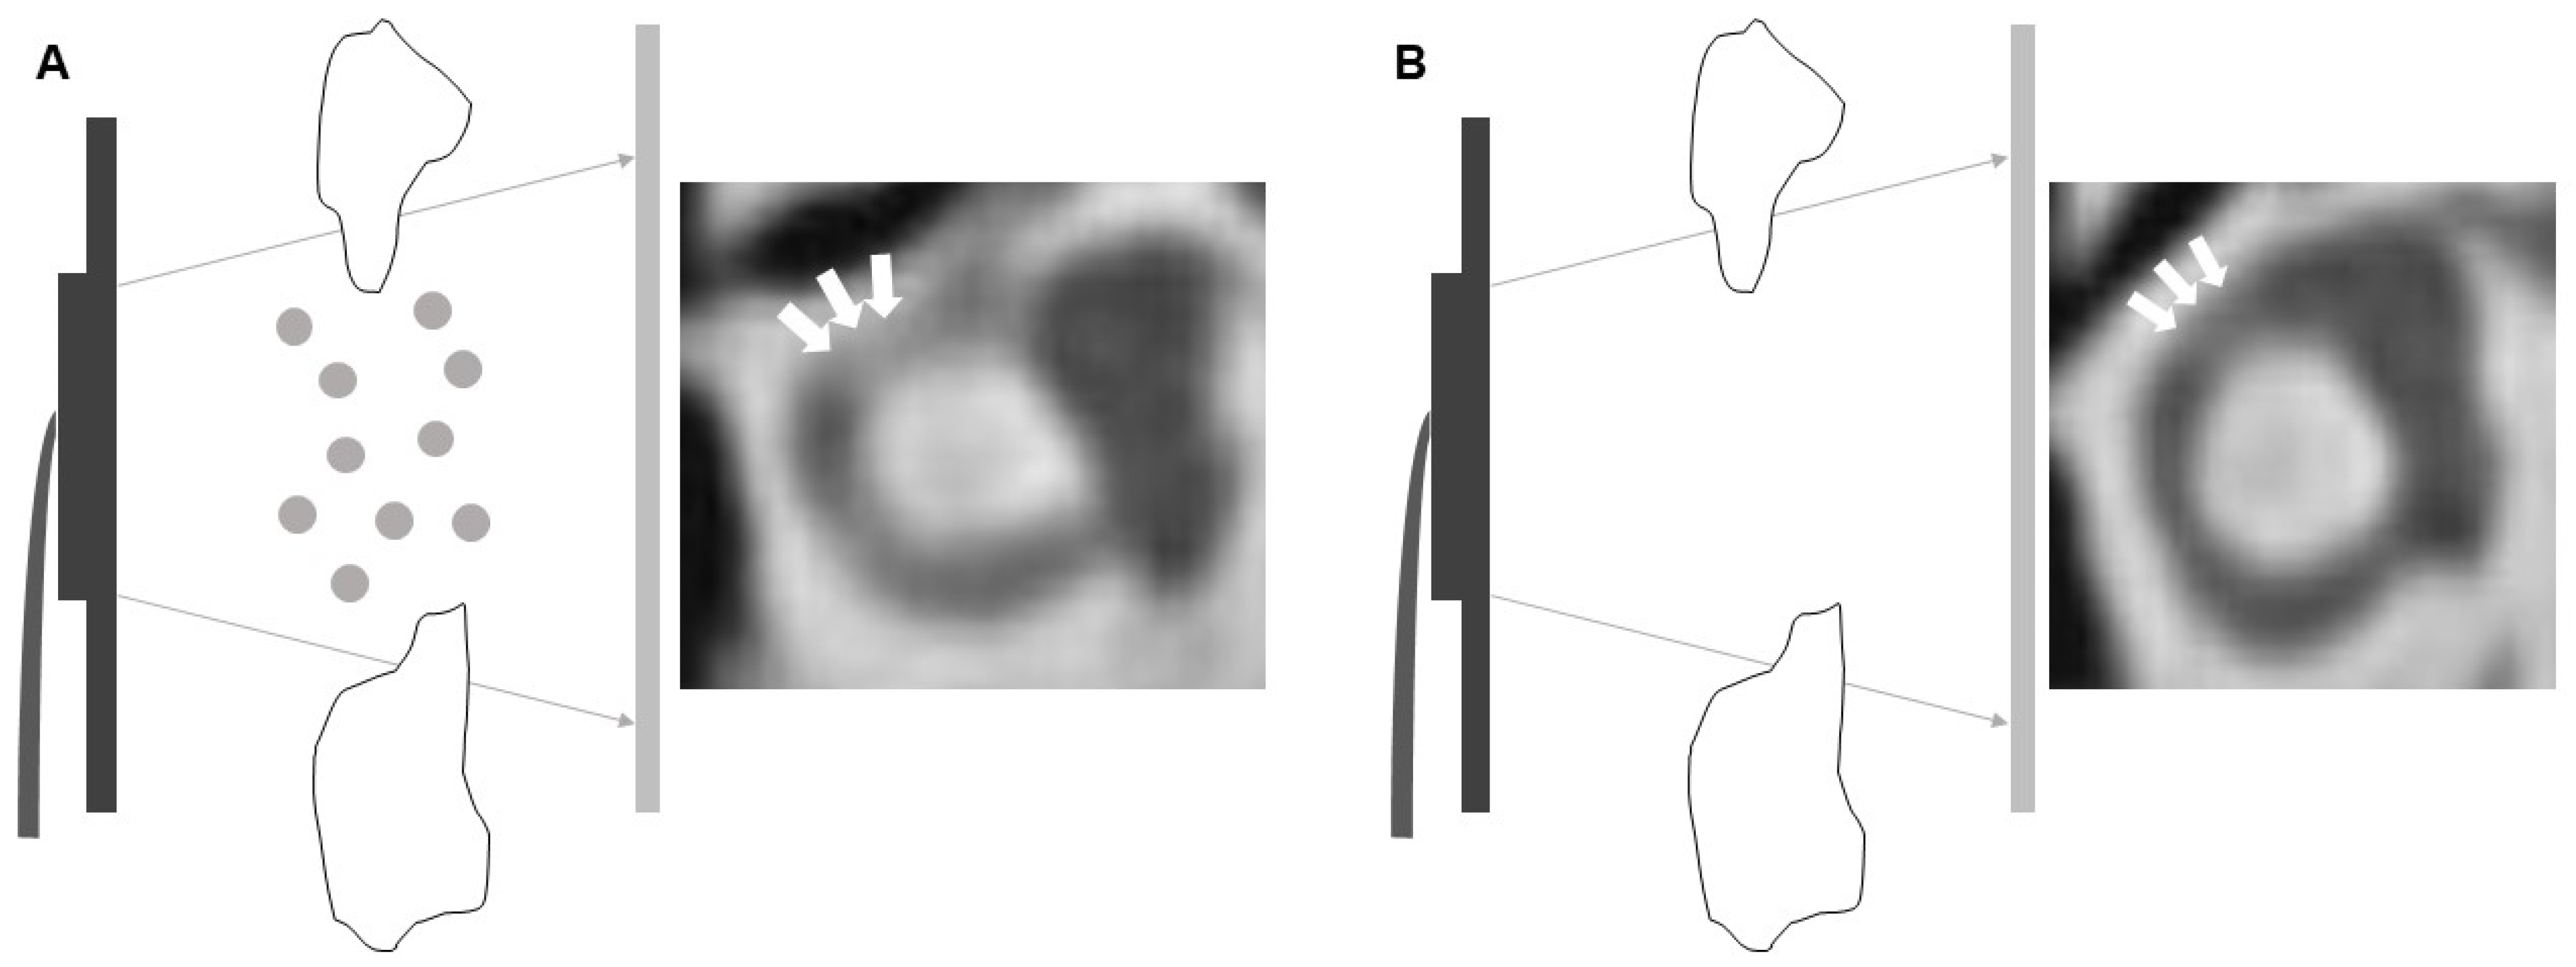

The Tyndall Effect in High-Resolution Computed Tomography of Semicircular Canalolithiasis with Benign Paroxysmal Positional Vertigo